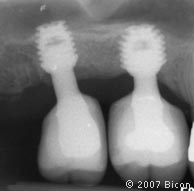

7. | 用两个6.0mm x 5.7mm短种植体支撑两颗烤瓷冠修复左下颌两颗磨牙。注意下齿槽神经管的水平。 |